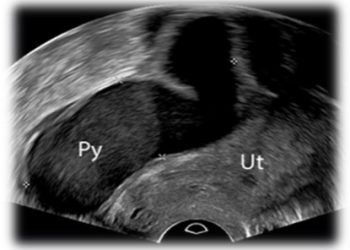

Cari soci, questo mese un nuovo video "How to do", dedicato alla classificazione ecografica dell'utero setto. Grazie a Daniela Giuliani!...